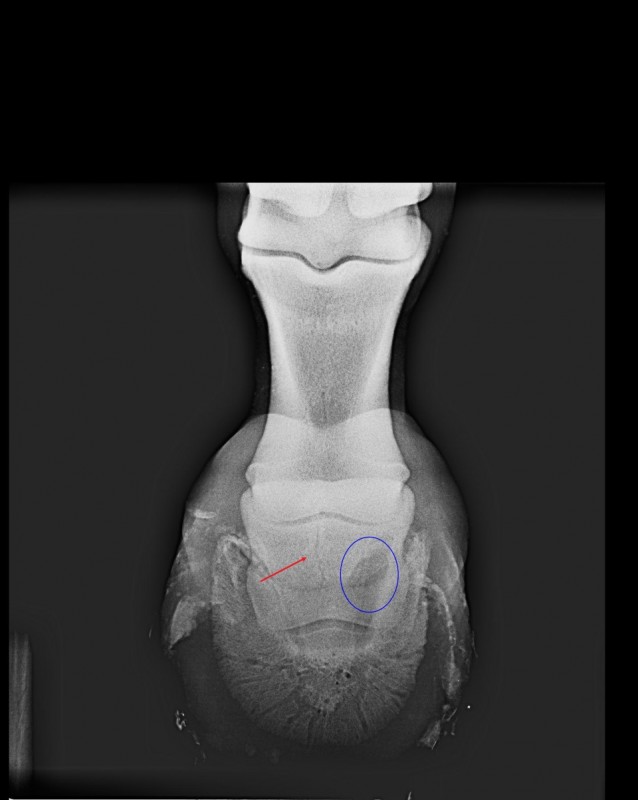

- il a été ferré régulièrement jusqu'à l'hiver de ses 4 ans. Le pied était plutôt bien revenu. J'ai donc décidé de le déférer pensant bien faire. 2 semaines après le déferrage grosse crise de fourbure. La radio de l'antérieur droit montrait un basculement de la 3ème phalange avec une forte décalcification osseuse. Sur les conseil du maréchal et du véto je l'ai laissé tranquille toute l'année suivante (ballade en main et travail en liberté en carrière)

- je viens d'effectuer une radio de contrôle (un an après) et le diagnostic n'est pas rassurant : "la troisième phalange est remaniée mais l'alignement est correct. On note toujours une zone suspecte de déminéralisation sur la vue de face. Nous vous conseillons la ferrure LAMINITIX de M. VAILLANT" (=110€ la ferrure...). Le vétérinaire m'a conseillé d'éviter les sols caillouteux (moi qui rêvais de partir en rando plusieurs jours). Il m'a vaguement parlé des injections de Tildren mais sans trop me rassurer sur leur efficacité. Aucune piste de solution d'un point de vu alimentaire (mon cheval est au foin tout l'année). A noter que maintenant le cheval présente une seime sur l'antérieur droit.

Je vous mets ci dessous les radios de l'antérieur droit ainsi que le visuel du fer conseillé.